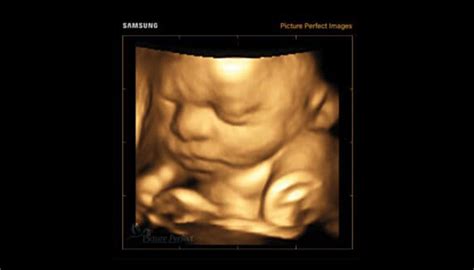

Ultimul trimestru de sarcină, care se întinde de la săptămânile 28 la 40, este o perioadă crucială pentru dezvoltarea fătului.

În ultimele trei luni, bebelușul trece prin schimbări fizice și fiziologice semnificative care îl pregătesc pentru viața în afara uterului.

În ultimul trimestru, fătul se confruntă cu o creștere rapidă.

Până la sfârșitul acestei perioade, bebelușul mediu cântărește între 2,5 și 4 kg și măsoară aproximativ 45 până la 56 cm lungime.

Copilul tău arată ca un nou-născut în miniatură.